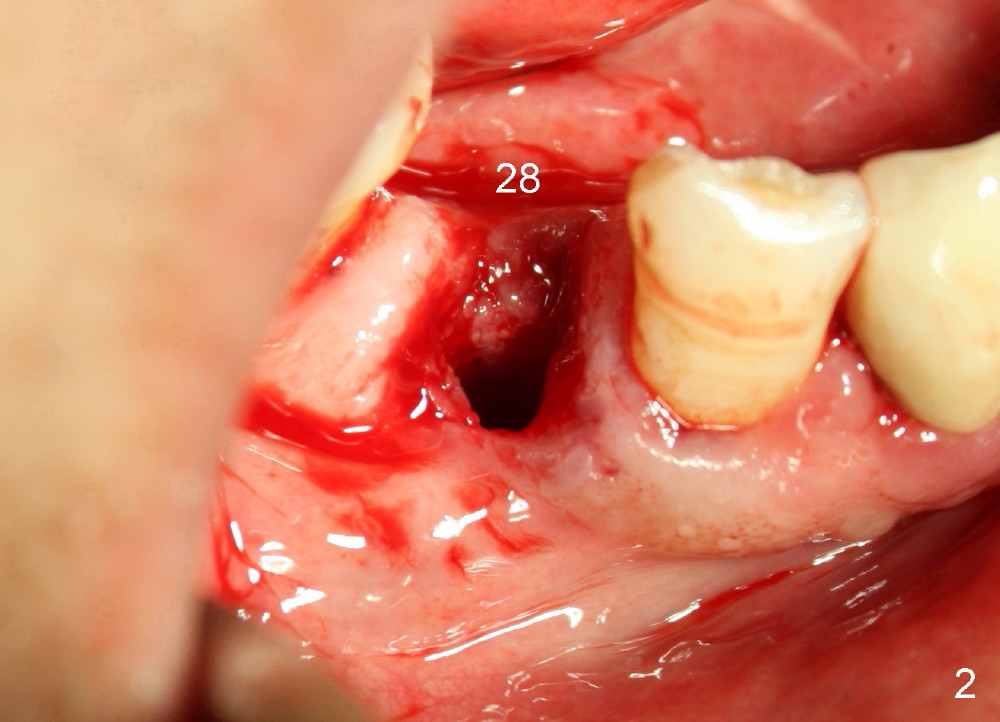

A 66-year-old man has poor dentition (Fig.1). Several teeth (x) including #28 need extraction and implants. The tooth #28 is extracted (Fig.2), followed by immediate implant (5x17 mm, Fig.3 I). There is more buccal gingival recession over the implant (Fig.4), which is less prominent 1.5 months postop (Fig.5). The definitive restoration is delivered less than 2 months postop (Fig.6), because of travel abroad. The patient agrees not to chew with the Emax crown. Five months later, he returns with chipped porcelain (Fig.7 arrowhead). It appears that immediate implant can survive early and over loading. More implants are necessary to share the masticatory loading. Since there is malocclusion, where to place implants appears to be critical (Model 3 30 4 5 6 7). There is no bone loss 4.5 years (Fig.8) or 5 years 8 months (Fig.9) post cementation.